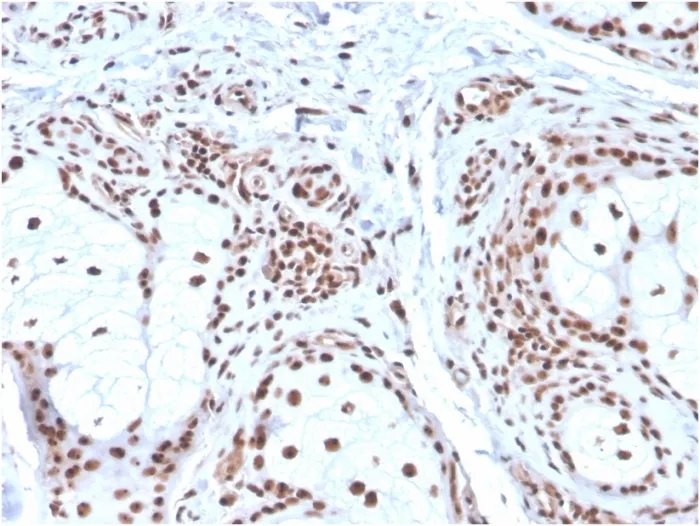

Recognizes a 33 kDa glycoprotein, identified as Nucleophosmin (NPM). It is predominantly localized in the nucleus of cells in most tissues. NPM is involved in ribosomal assembly and rRNA transport. It is an abundant protein that is highly phosphorylated by Cdc2 kinase during mitosis. This phosphoprotein moves between the nucleus and the cytoplasm. It is thought to be involved in several processes including regulation of the ARF/p53 pathway. A number of genes are fusion partners, in particular the anaplastic lymphoma kinase gene on chromosome 2. Mutations in exon 12 affecting the C-terminus of the protein are associated with an aberrant cytoplasmic location. Mutations in this gene are associated with acute myeloid leukemia. The antibody may be a useful aid for classification of acute myeloid leukemia. Primary antibodies are available purified, or with a selection of fluorescent CF® Dyes and other labels. CF® Dyes offer exceptional brightness and photostability. Note: Conjugates of blue fluorescent dyes like CF®405S and CF®405M are not recommended for detecting low abundance targets, because blue dyes have lower fluorescence and can give higher non-specific background than other dye colors.Synonyms:

Flow, intracellular (verified) | IF (verified) | IHC, FFPE (verified) | WB (verified)Validated Applications:

K562 cells, Human colon or skin tissues (IHC).Concentration: